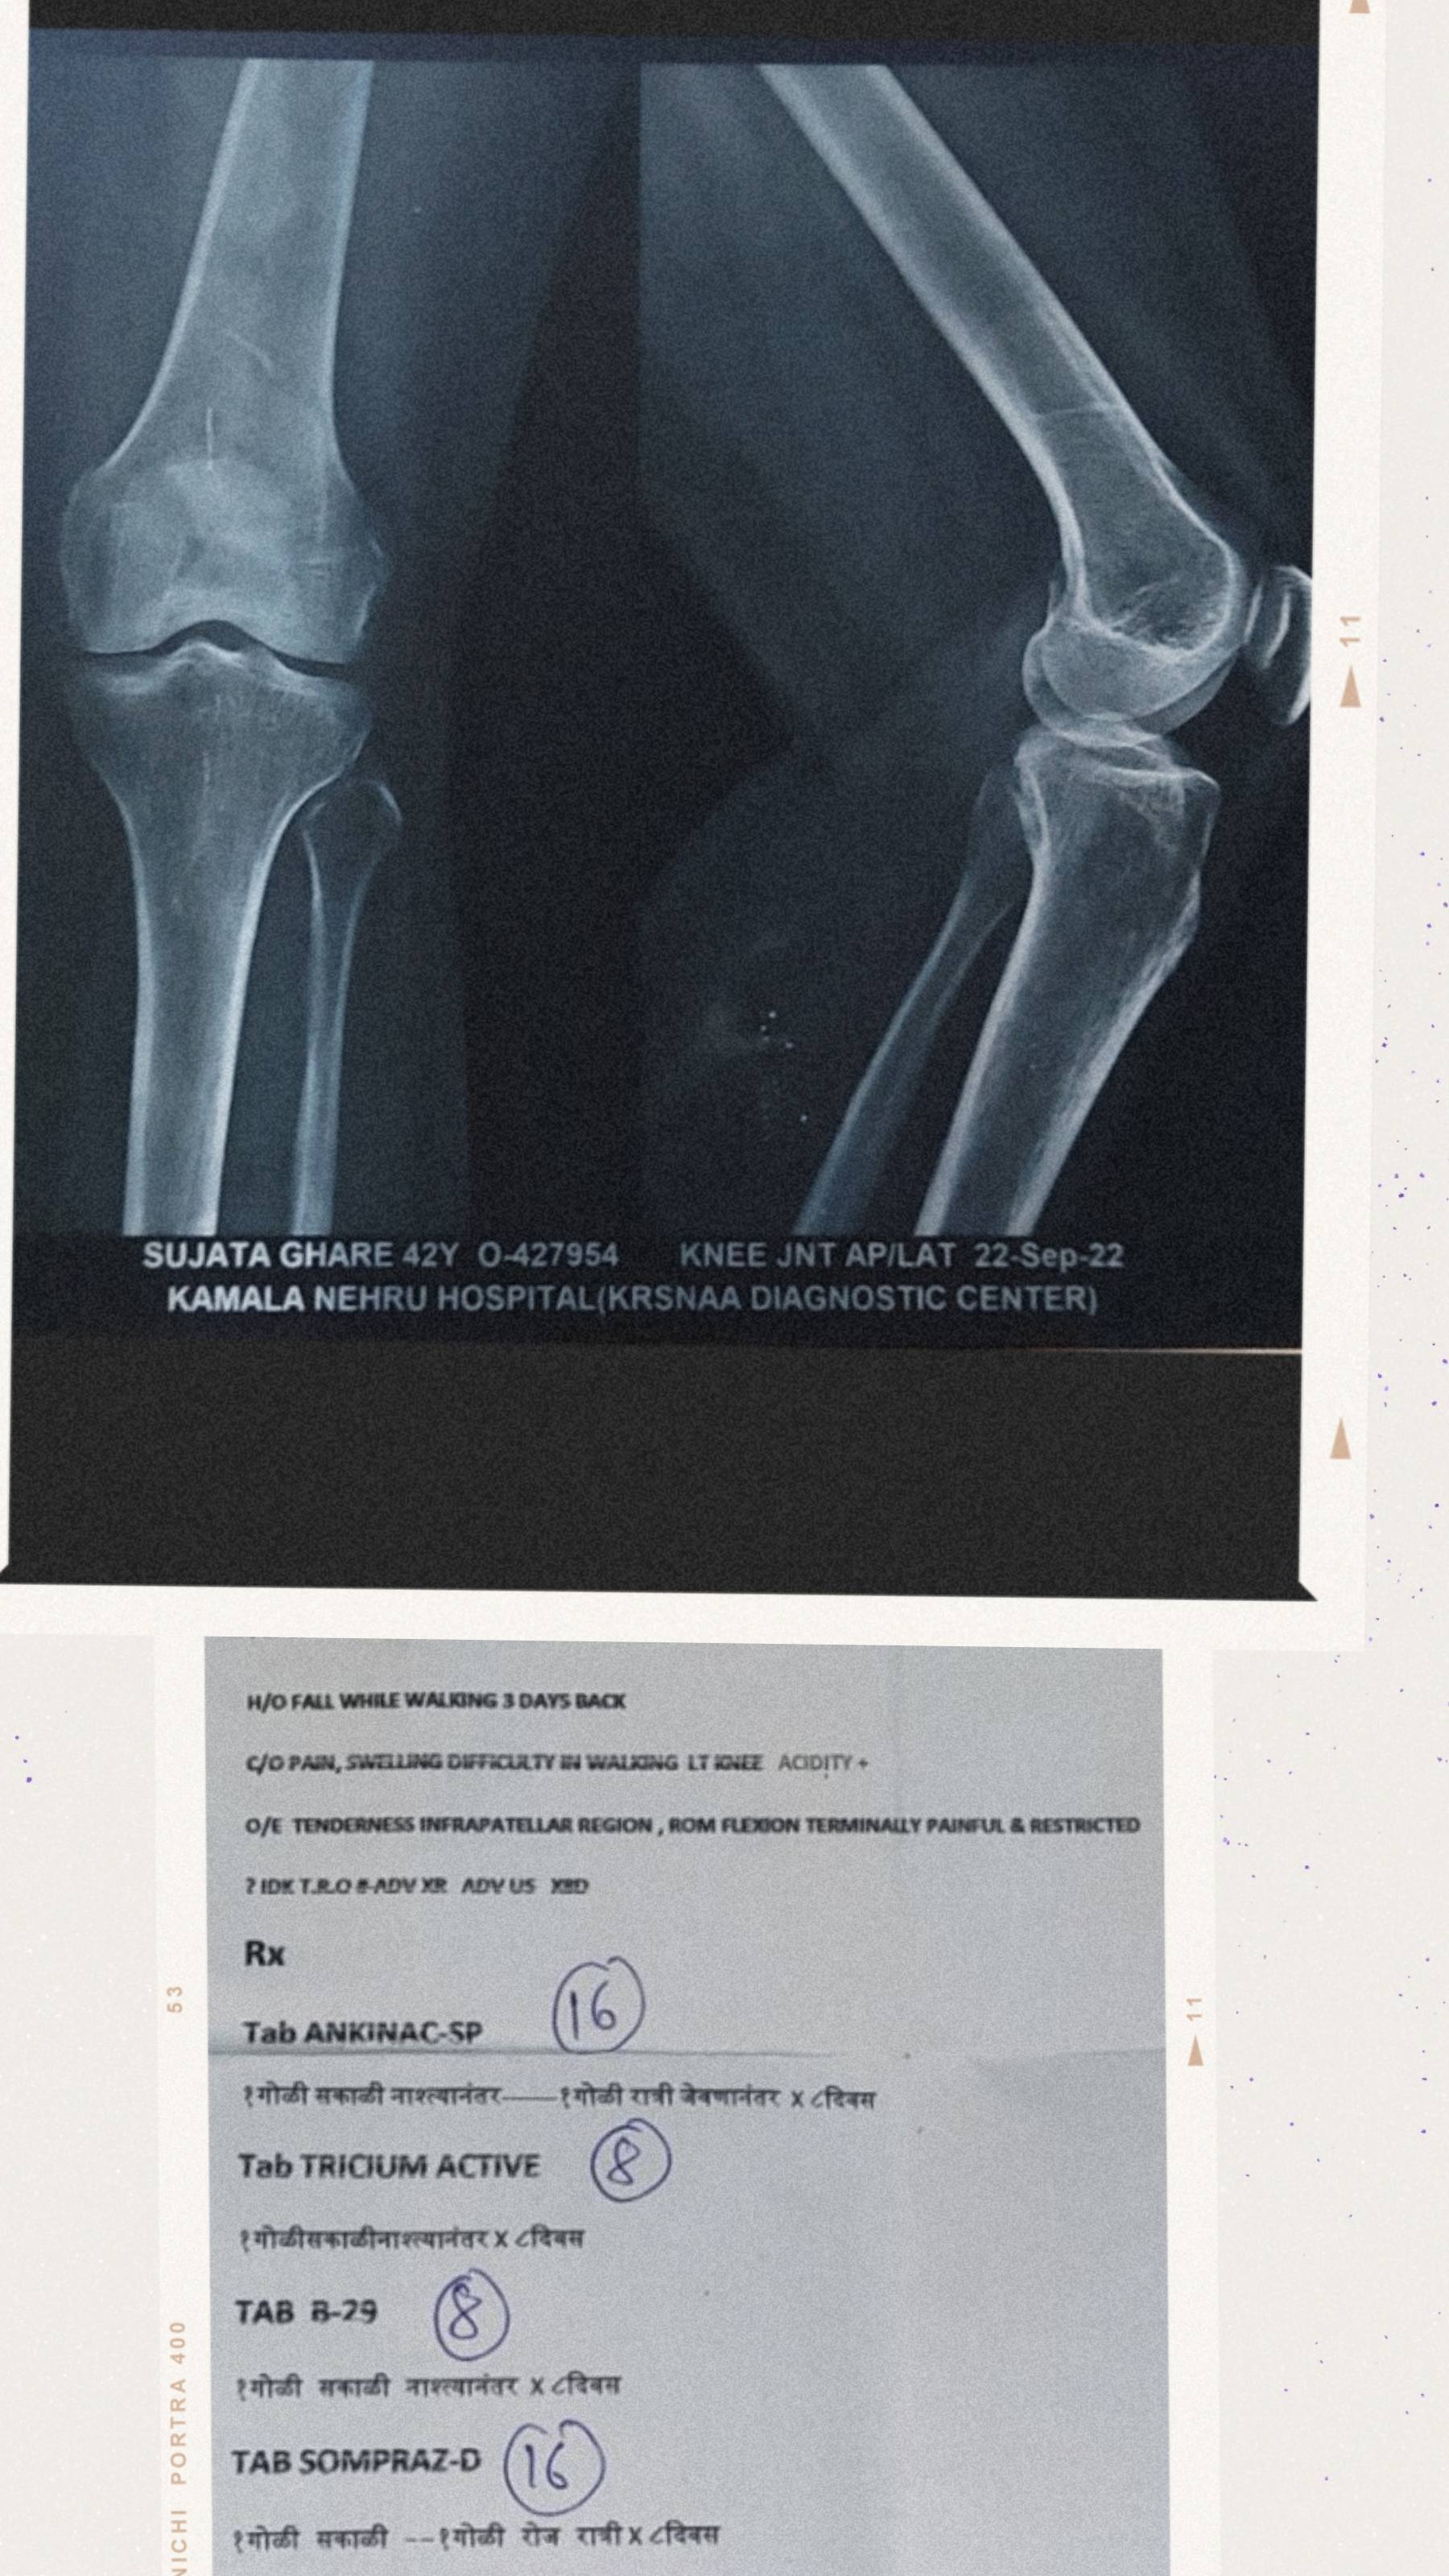

Since Last 3 months..I am having severe pain in my left knee. Xray reports are  saying that it's a hit to bone( I have attached the report kindly take a look), according to doctor and his guidelines I did followed the physiotherapy for pretty long time. Follow some regular exercises too, since there is no improvement.

While walking accidentally my left leg got folded backwards and caused pain in my knee..for few days I wasn't able to stand and walk..after 3 months now I can atleast walk a little bit and fold my leg at knee(roughly) still I can't climb stairs, and inflammation occurs behind my knee which causes pain. Can't stand for long time.

Since Last 3 months..I am having severe pain in my left knee. Xray reports are totally normal, according to doctor and his guidelines I did followed the physiotherapy for pretty long time. Follow some regular exercises too, since there is no improvement.